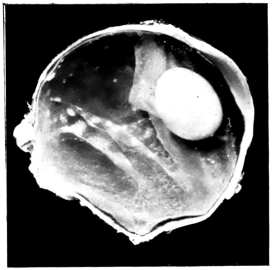

PLATE II.

FACING

PAGE

10.

LENS DISLOCATED BETWEEN CILIARY BODY AND SCLERA

curly bracket span

38

11.

NUCLEUS OF CATARACT FREELY MOVABLE BETWEEN THE AQUEOUS AND VITREOUS CHAMBERS

12.

LENS IMPACTED IN ANGLE OF ANTERIOR CHAMBER

13.

CAPSULE OF MORGAGNIAN CATARACT IMPACTED IN ANGLE OF ANTERIOR CHAMBER

14.

LENS FLOATING FREE IN VITREOUS CHAMBER

15.

LENS LIGHTLY IMPRISONED IN EXUDATE INTO VITREOUS CAVITY